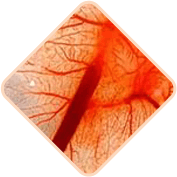

Daño en los vasos

sanguíneos

del recto

Los vasos sanguíneos dilatados en las hemorroides pueden sufrir daños y romperse, aumentando el riesgo de hemorragia. La severidad de la hemorragia puede variar desde leve hasta severa, requiriendo cirugía o incluso transfusiones de sangre.

Las hemorroides crónicas pueden causar la formación de coágulos en los vasos sanguíneos. Con el tiempo, estos coágulos pueden desprenderse y obstruir los vasos de otros órganos internos, causando accidentes cerebrovasculares, embolia pulmonar y tromboembolia coronaria.